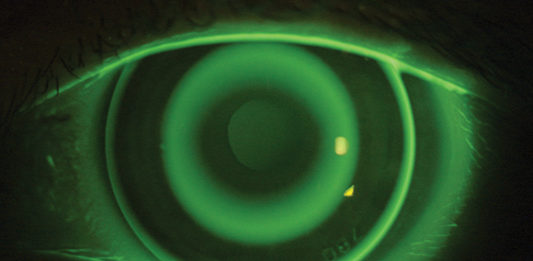

CSO porta innovazione e design al 42° Congresso internazionale ESCRS

CSO – Costruzione Strumenti Oftalmici – ha partecipato alla 42esima edizione di ESCRS (The European Society of...